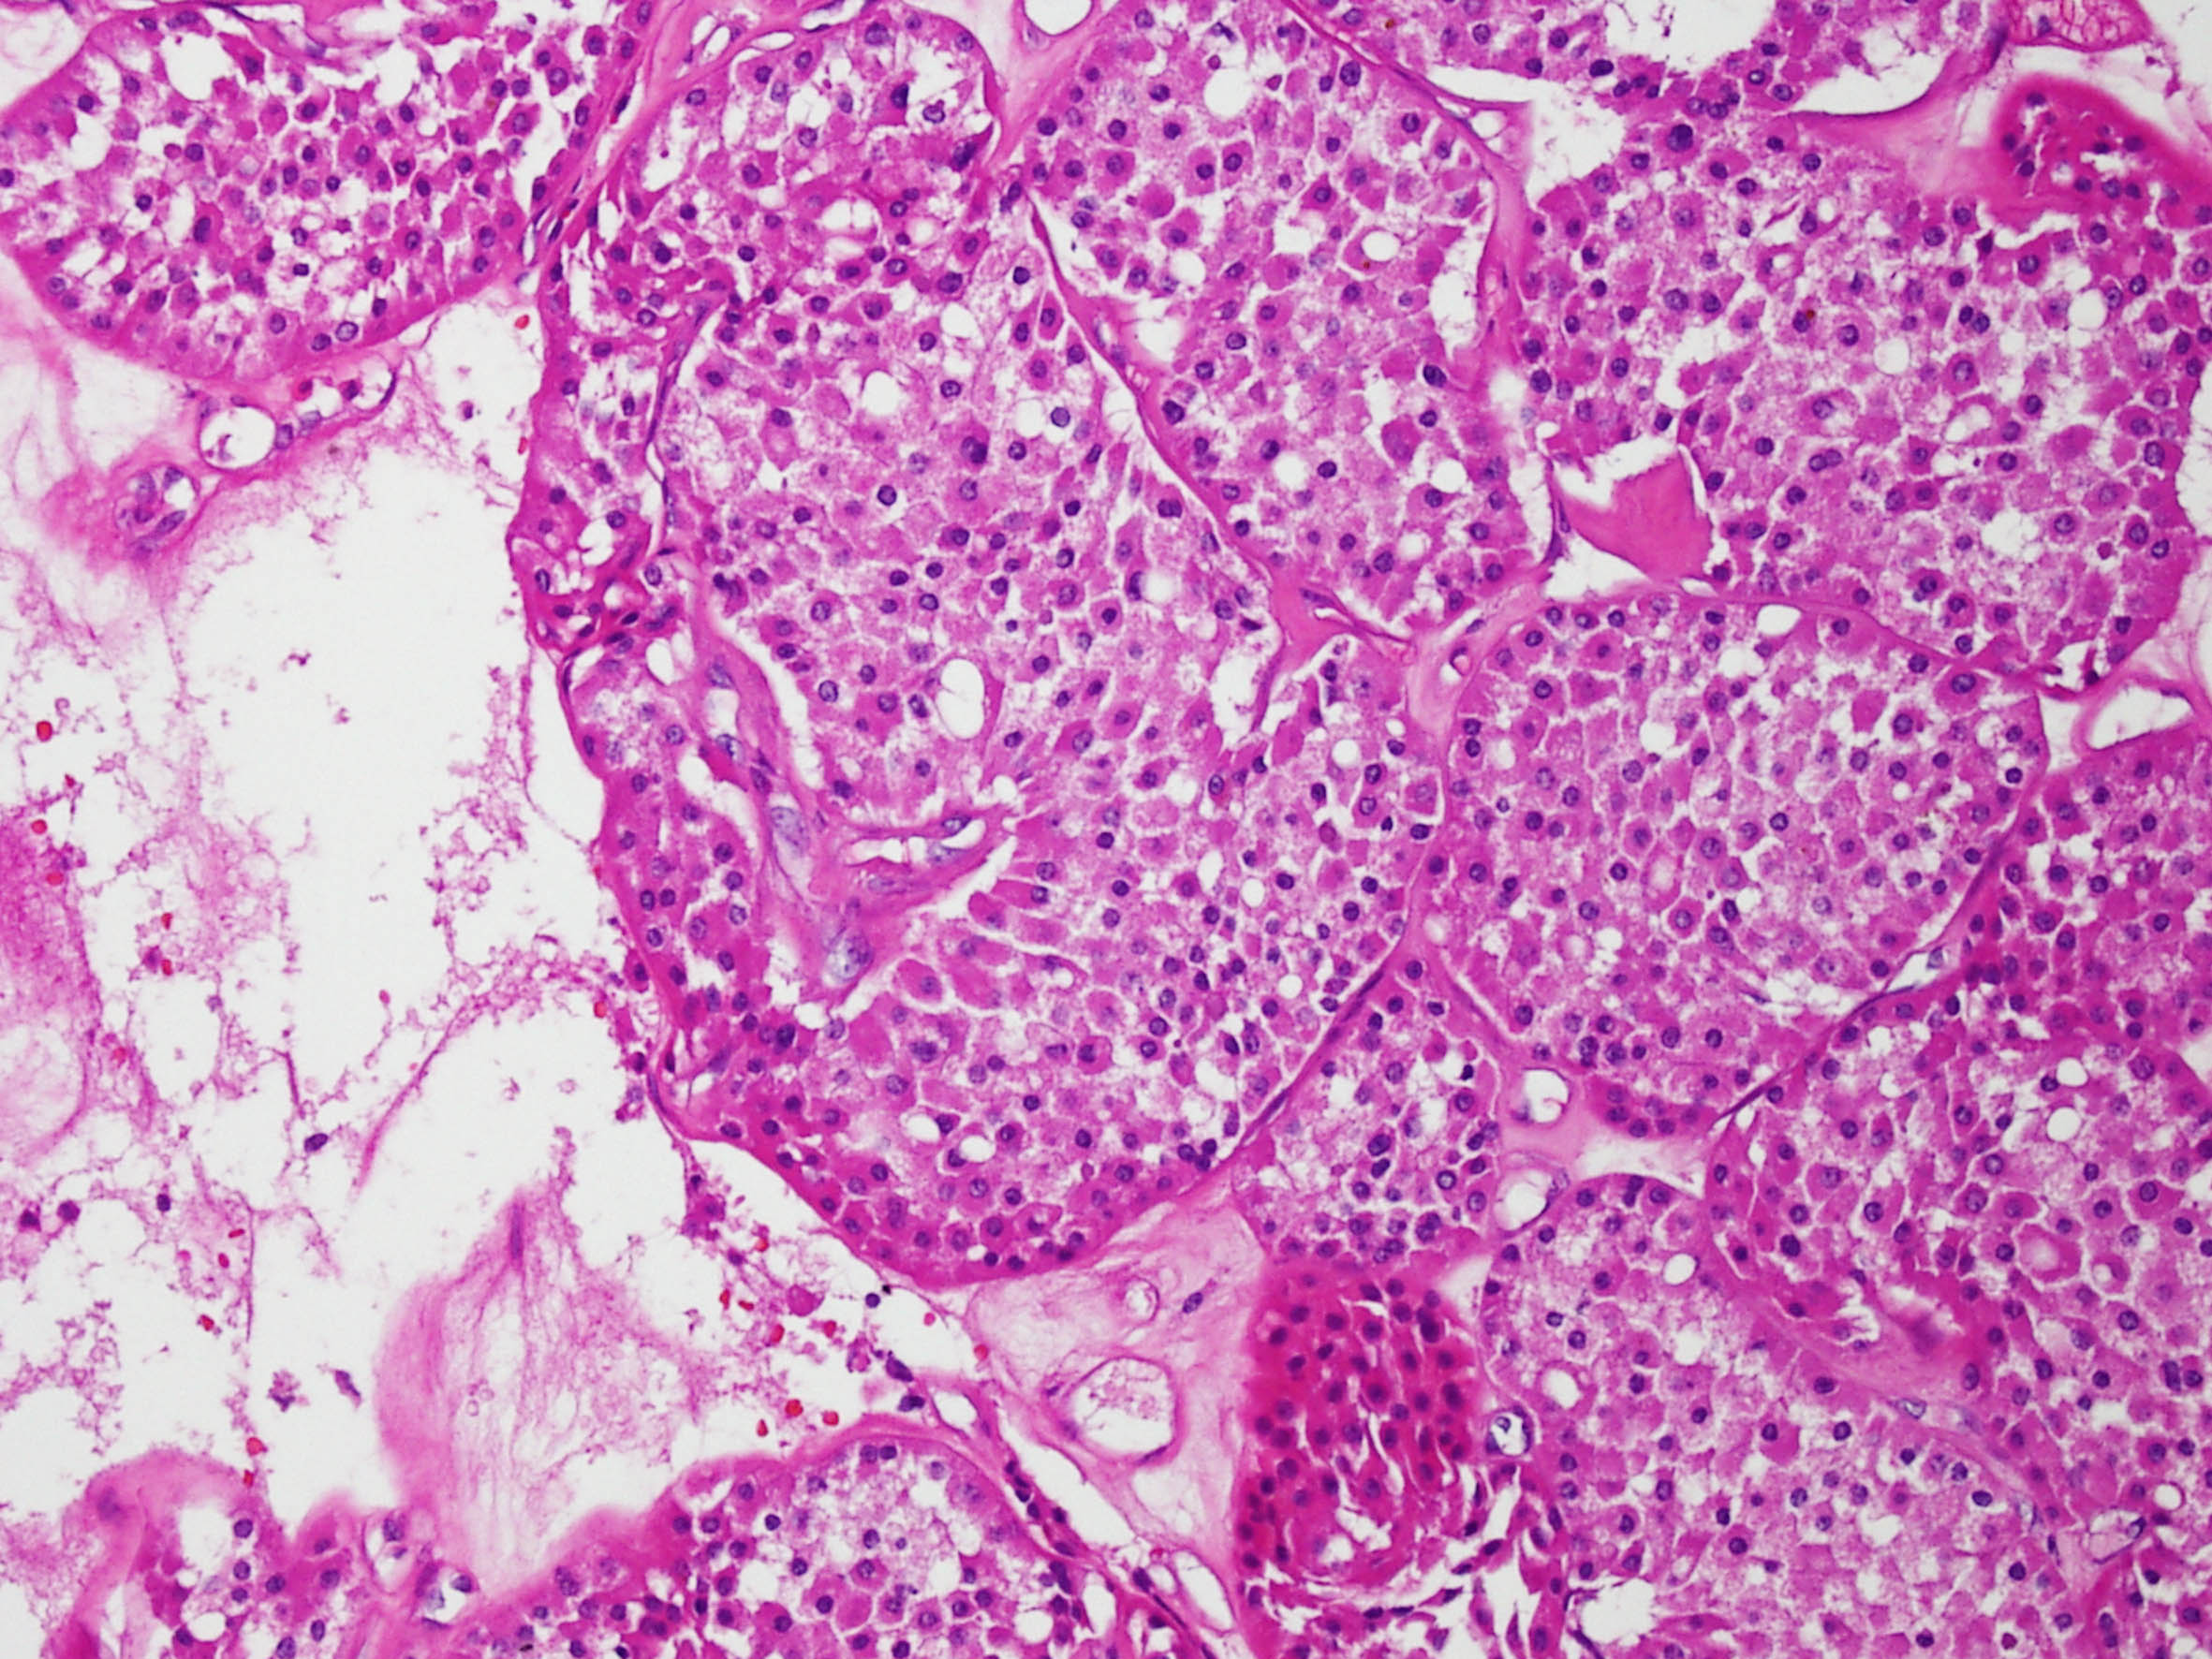

Renal tumor grading

Case ID: 290